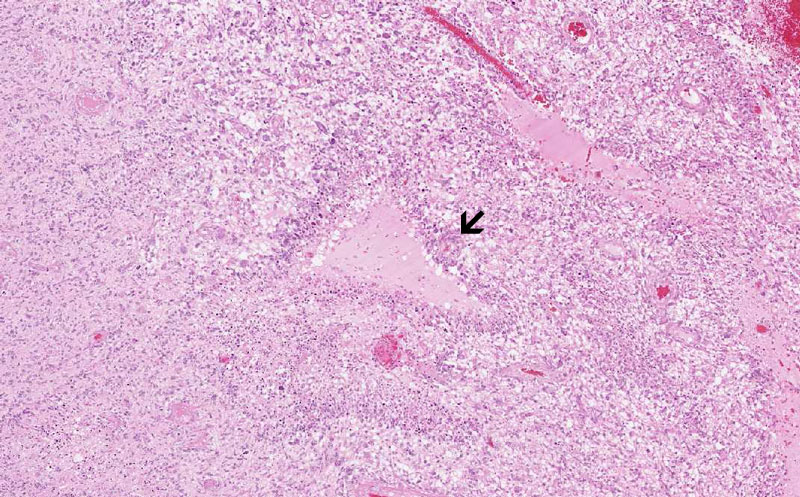

Hematoxylin & eosin

Area 1: Pseudopalisading necrosis (arrow) is one of the characteristics of glioblasoma. They typically occur as triangular (as illustrated here) or slit like necrosis ( as illustrated in other areas of this slides). Note that there is neoplastic proliferation of glial cells in the background.

• This is basically a high grade glioma feature by pseudopalisading necrosis (Area 1) and endothelial proliferation (Area 2). The prognosis for this type of tumor is extremely poor,.